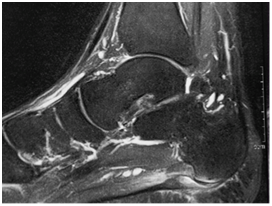

At the same time, imaging examinations were requested: Magnetic Resonance (MRI) of the foot 24 hours after the injury on the court 03/03/2017 Figure 2, 3 showing signs of acute traumatic rupture of the plantar fascia at calcaneus origin, with small plantar net collection without significant shrinkage. Central plantar fasciitis is associated with fusiform thickening of the fibers and degeneration area near the origin of the calcaneus, close to the area of traumatic rupture.

Figure 2 & 3 Magnetic Resonance of the foot performed with multiplanar cuts of 4.0mm showing signs of acute traumatic rupture of the plantar fascia at the calcaneus origin.